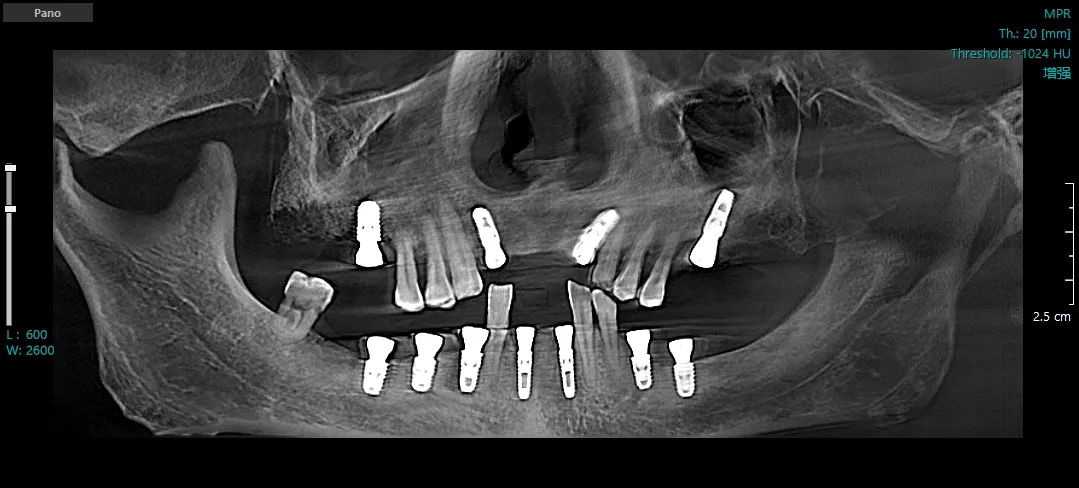

种植后CBCT三维重建图

65岁的张先生,因全口缺牙多年,日常咀嚼功能严重受影响,日前到楼凤网 中医医院口腔科就诊,口腔科主任乐涛检查后发现,张先生口腔基础条件差,牙槽骨吸收严重,这给牙齿修复带来了困难。乐涛凭借着丰富经验和精准操作,通过口腔颌面锥形束CT三维重建技术(CBCT)和口腔3D扫描技术,精准获取了患者口腔的三维模型,掌握了患者口腔血管、神经位置及牙槽骨的吸收情况,并运用种植导板定位技术,成功为张先生种植了11颗前牙,种植成功的当天患者即可正常咀嚼食物。